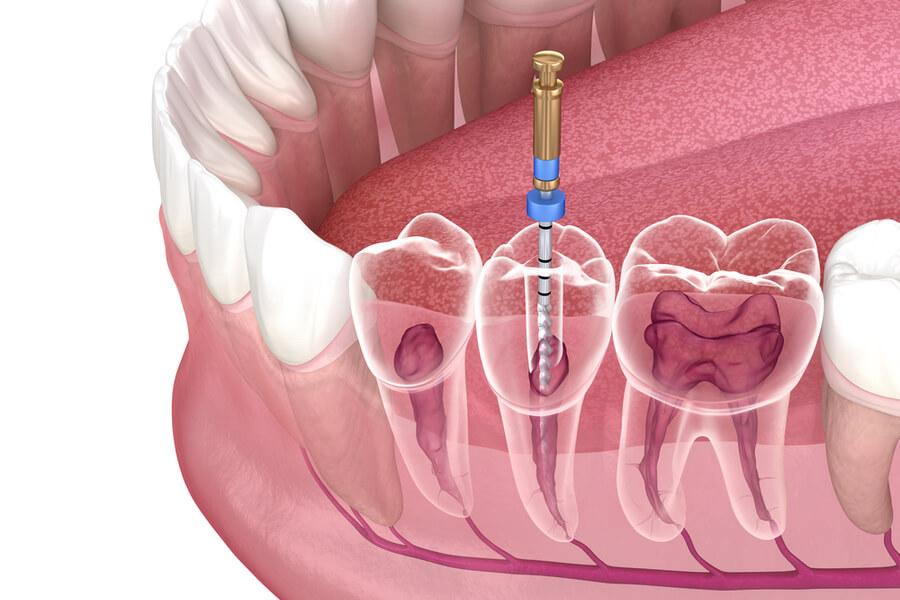

Root Canal Filling

The inflamed nerve is cleaned, and then the canals are filled safely to prevent the pain from recurring. At our clinic, we use the latest techniques for root canal treatment to save the tooth from extraction.